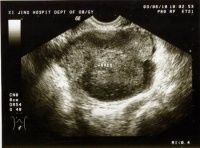

(一)B超:可明确肿瘤的大小形态囊实性部位及与周围脏器的关系鉴别巨大卵巢囊肿及腹水